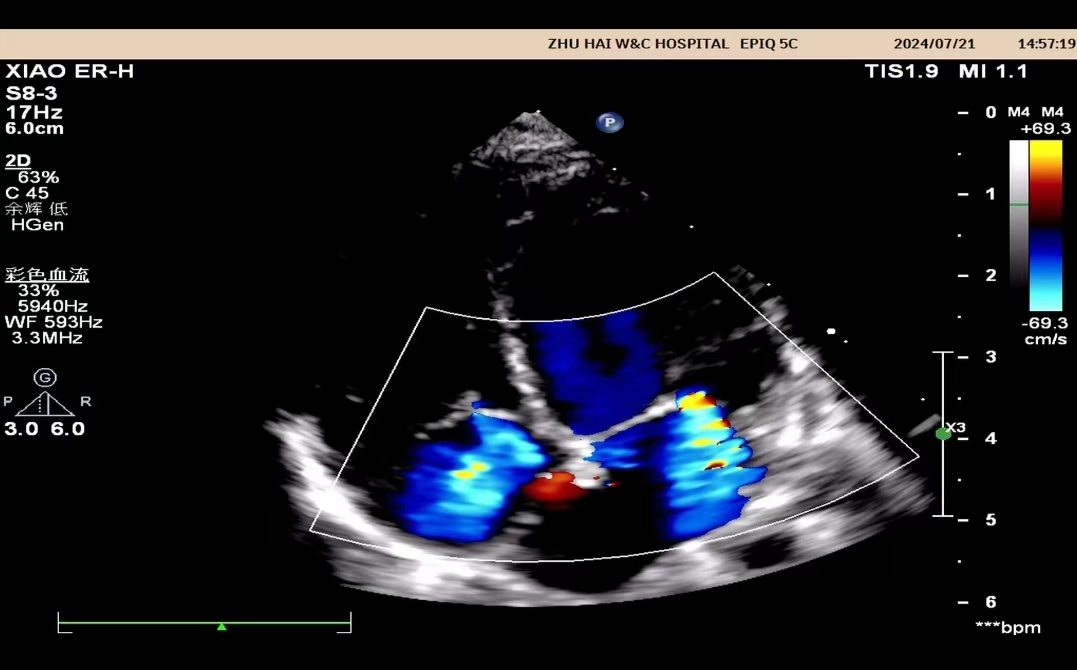

什么是心脏彩超?

心脏彩超是能够动态显示心腔内部结构、心脏搏动和血液流动情况的一种无创性检查技术。通俗地说,心脏探头有点类似于摄像机的镜头,通过镜头的不断移动和变换,让心脏的各个结构得到准确的呈现,从而让医生能够根据这些图像判断心脏是否存在问题。

大部分都可以通过心脏彩超查出,例如:房间隔缺损,室间隔缺损,动脉导管未闭,心内膜垫缺损,法洛四联征、大动脉转位等。

心脏彩超除了对于先天性心脏病有比较好的显示效果外,对于后天因素所导致的心脏病,同样能够有很好的诊断效果。比如常见的瓣膜狭窄、瓣膜关闭不全、风湿性心脏瓣膜病、冠心病、肥厚型心肌病、扩张性心脏病等。